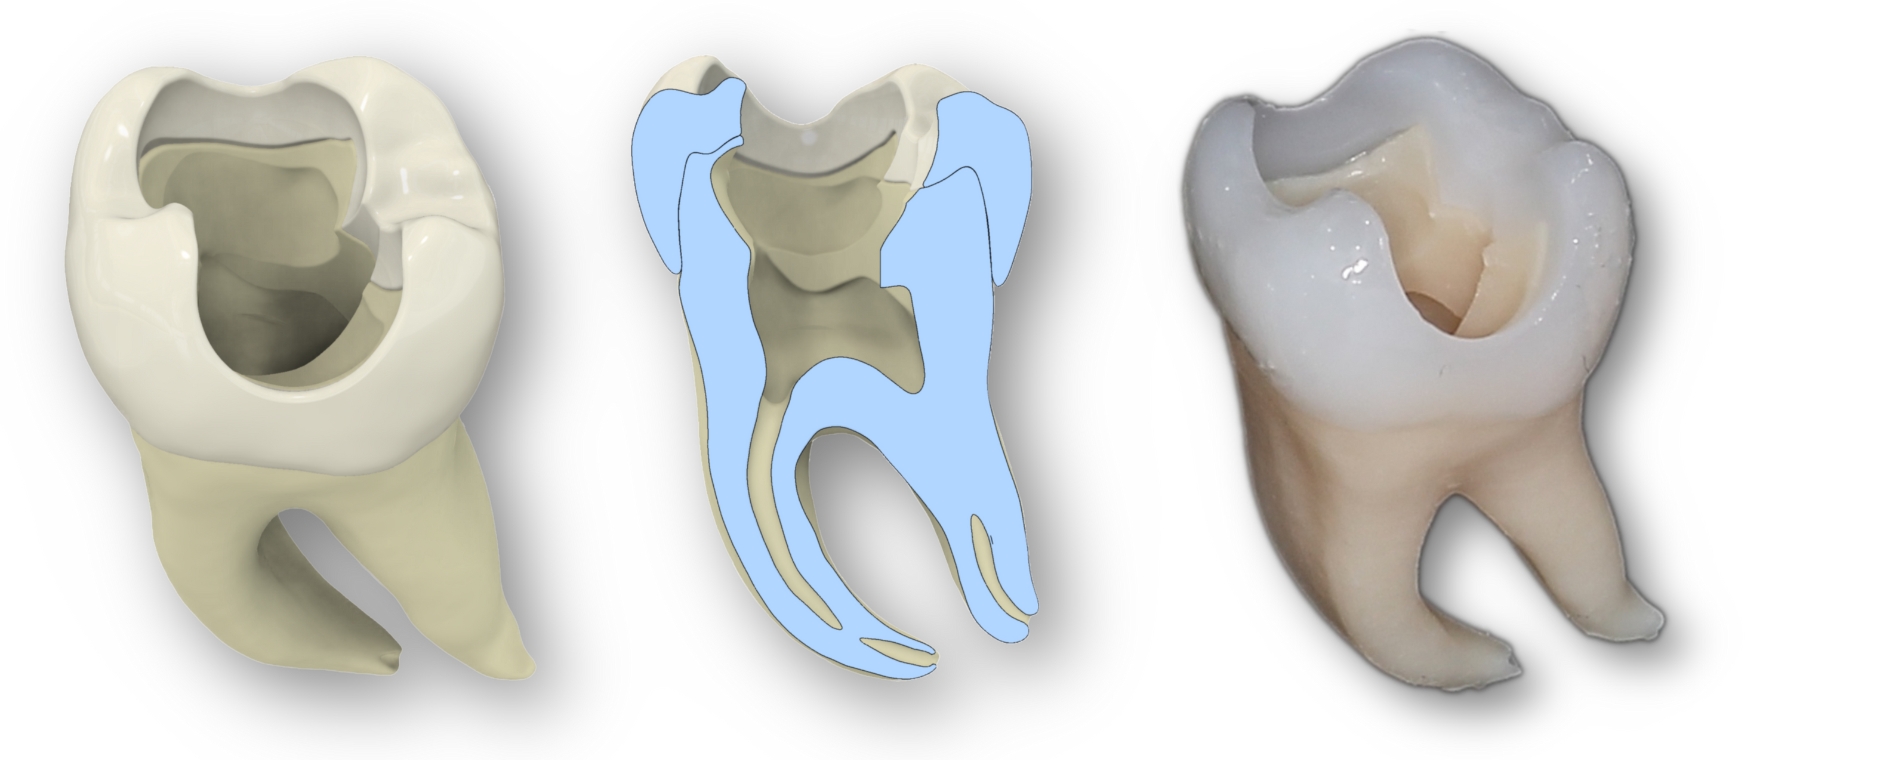

Studien belegen den hohen Lerneffekt, die Akzeptanz bei Studierenden und den didaktischen Nutzen des universellen Übungszahns bei einer Kariesexkavation und beim Präparieren von Klebebrücken belegten bereits Studien im Journal BMC Medical Education und in Scientific Reports. Jetzt wurde die Erprobung des 3D-gedruckten Zahns bei der Wurzelkanalbehandlung veröffentlicht.

38 Zahnmedizinstudierende bewerteten den 3D-gedruckten Zahn als eine signifikant bessere Übungsmöglichkeit als die üblichen transparenten Acrylblöcke, die oft zum Üben für Wurzelkanalbehandlungen zum Einsatz kommen, und fast ebenbürtig zu natürlichen Zähnen, insbesondere hinsichtlich Realismus, Handhabung und Lernwert. „Der gedruckte Zahn ist nicht nur realistisch und kosteneffizient, sondern auch fair. Mit dem neuen Übungszahn haben wir für alle Studierenden identische Prüfungs- und Lernbedingungen geschaffen“, resümiert Erstautorin Isabella Di Lorenzo.

Auch Oberarzt Dr. Michael del Hougne M.Sc., Kursleiter im Bereich der klinischen Lehre, ist vom neuen Übungszahn begeistert. „Unsere Studierenden können an dem Modell sogar die elektrische Längenmessung des Wurzelkanals sehr realistisch üben. Dafür mussten wir jedoch etwas tricksen, um die benötigte Leitfähigkeit herzustellen, denn der Zahn ist aus Harz, das den Strom nicht leitet.“ Im nächsten Schritt sollen 3D-Zähne mit unterschiedlichen Wurzelkanalformen entwickelt werden, um die klinischen Herausforderungen, die sich aus der anatomischen Vielfalt ergeben, zu simulieren.